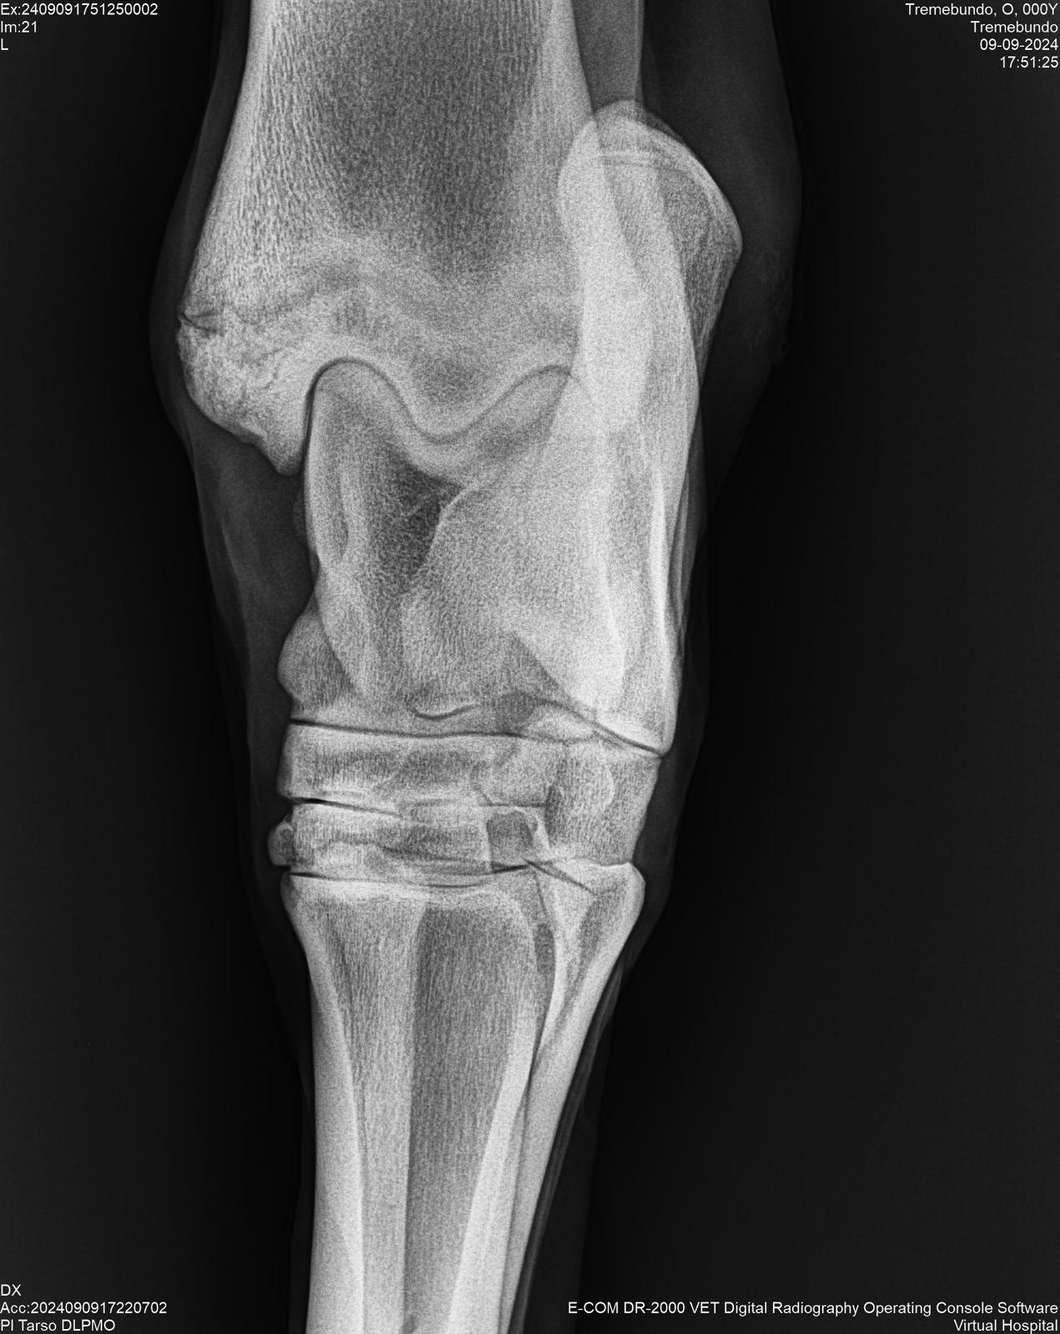

LOTE 37, TREMEBUNDO

Identificador: #291140-

Generacion 2022